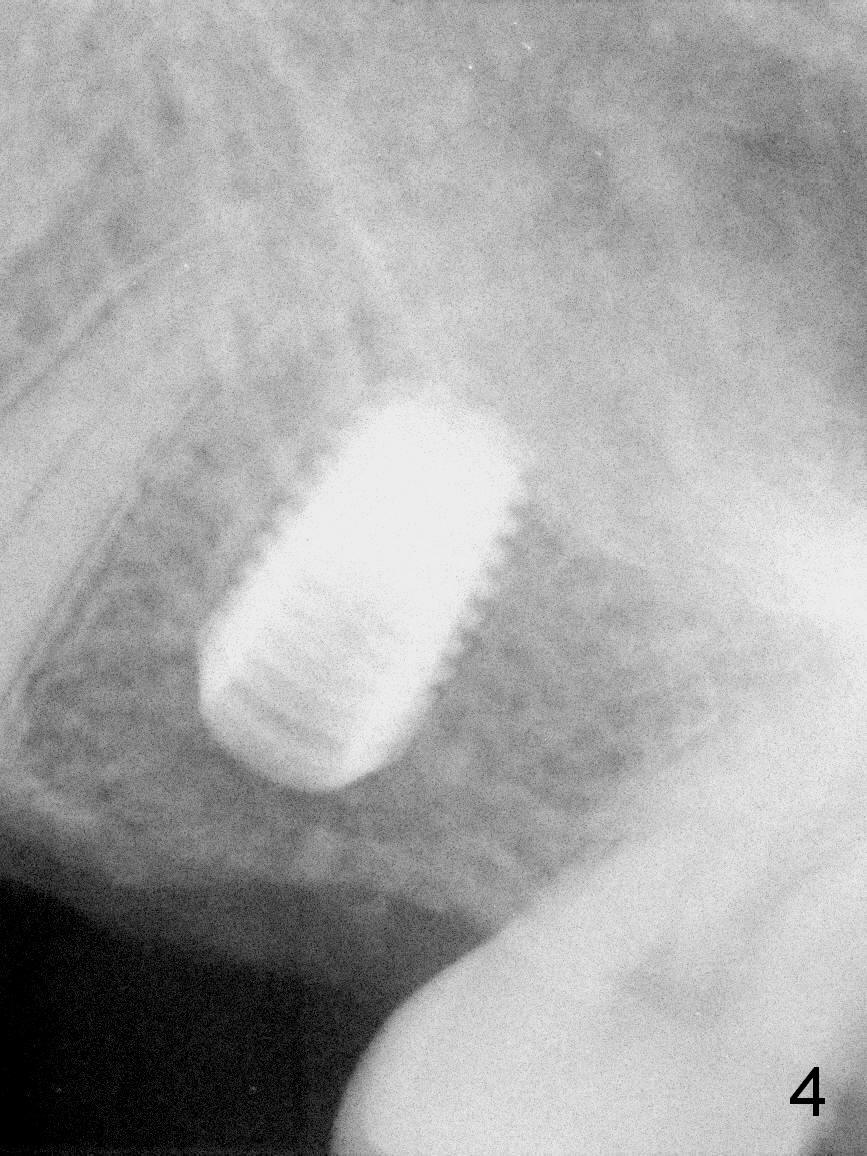

A 49-year-old man is an engineer. The tooth #14 is missing (Fig.1,2). He wonders how a one-rooted implant can replace a three-rooted tooth. Anyway, osteotomy is initiated at the site with 2.5 mm reamer in place (Fig.3). A 5x8 mm Bicon implant is placed (Fig.4). Seven and a half months later, the bone density next to the implant plateau appears to increase (Fig.5 arrowheads, as compared to Fig.4). The beauty of Bicon implant is that the crown (Fig.6 C) can be extraorally cemented to the abutment (A) prior to re-seating. Two years and 3 months post cementation, while no residual cement is visible, the bone density at the crest has increased (Fig.7 arrowheads). The crown is de-cemented 4 years 4 months post cementation; it appears that the abutment is small and short (5x2 mm 10 degree stealth). The bone density of the cortex around the implant (Fig.9 ^) is higher than that at #15 and #3.